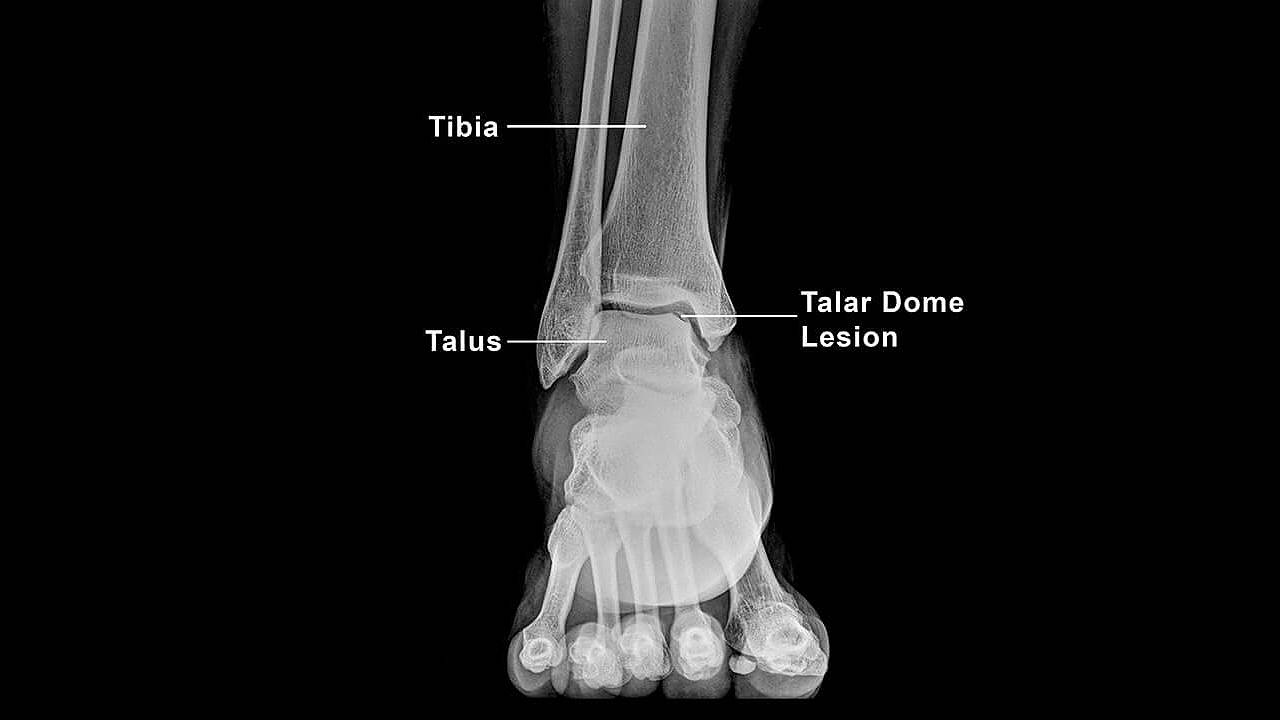

The talus bone, which is the part of the ankle that enables smooth movement, has a dome-shaped top covered in a layer of cartilage. An injury can cause damage to this area and the underlying subchondral bone, resulting in a talar dome injury typically referred to as an osteochondral lesion or defect. While injuries commonly present on the inside or medial aspect of the ankle, the outer ankle can be affected as well.

X-rays or an MRI of the ankle are performed to diagnose and determine the size, extent, and stability of the talar dome lesion or injury. The application of non-invasive podiatric intervention depends on several factors: